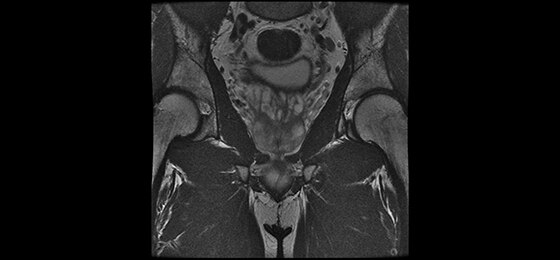

A large usable field of view is needed to properly image off-center anatomy such as a shoulder or hip. So the Discovery* MR750w features a 70 cm flared, open bore design with a large 50 x 50 x 50 cm field of view.

GEM Posterior Array - Embedded high-density posterior array with optimal coil element geometry that enhances spine, abdomen, cardiac, and lower extremity scanning.

GEM Anterior Array - A lightweight, flexible, thin and pre-formed array to embrace patients’ various sizes and shapes. With 54 cm of S/I coverage, the anterior array permits upper abdominal and pelvic imaging without repositioning the patient and supports parallel imaging in all 3 planes.